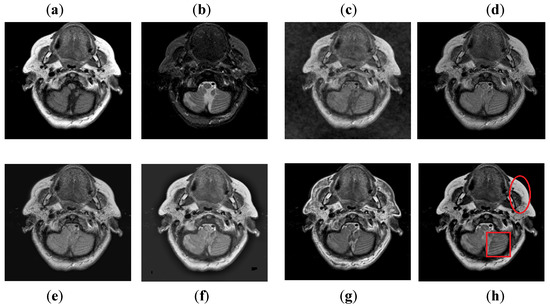

It can be seen in Figure 10 that DCT has poor results with more artifacts. The DWT method also has artifacts and pixel discontinuities due to limited directional information. The image obtained by NSST-SF-PCNN has better visual effects, but it has uneven illumination, and due to that, the fused image lost some vital information. The CSR and CNN methods resemble each other, but the contrast of CNN is better than CSR. Both methods acquire good visual results and have good image contrast, but some edges and boundaries are not vivid. The proposed method again shows its supremacy by producing output image with vivid contrast and high resolution. Additionally, it can be depicted in red boxed to capture smooth edges and contours more precisely.

Figure 10. Data-4: (a) CT image, (b) MRI image, (c) DCT, (d) DWT, (e) NSST-SFT-PCNN, (f) CSR, (g) CNN, (h) and Proposed.